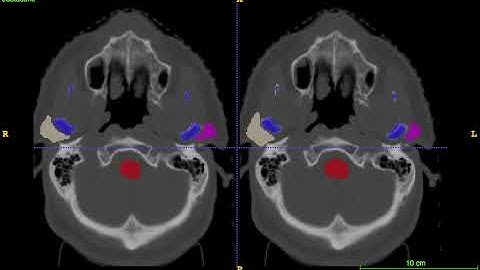

AnatomyNet-for-anatomical-segmentation test demo 3